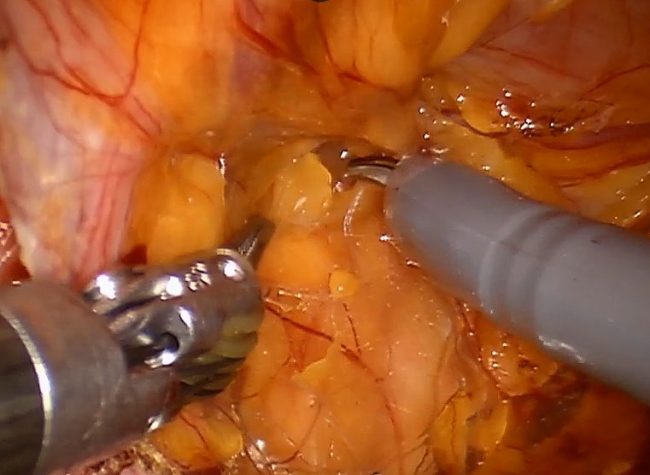

Robotic assisted repair of recurrent right inguinal hernia with mesh

This is a 52 year old male with history of right inguinal hernia repair 10 years ago who presented with a painful bulge in the right groin. Patient underwent a robotic assisted repair of recurrent right inguinal hernia with mesh. There was an evidence of recurrent right inguinal hernia on the most medial aspect of the pervious hernia repair with incarcerated pre-peritoneal fat in the hernia defect.